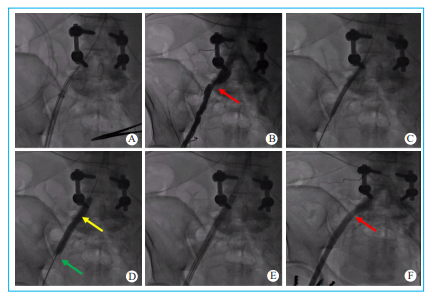

沿150cm冠脉下肢导丝,送入第一把ProGlide,然后撤出冠脉下肢导丝。调整ProGlide至1点方向(正上偏内10°)后推入主入路动脉。待侧孔喷血后再推进少许,然后向上提扳手(1号标记)。回撤ProGlide至感到线脚抵触到血管壁,此时增大ProGlide与皮肤的角度至约 45°,保证血管内的针脚与血管前壁充分贴合。左手上提ProGlide并维持住张力,右手按下针柄(2号标记)。拔出针柄(3号标记),轻拉缝线,然后将缝线绕至剪刀处剪断。将扳手关闭(4号标记),整体往外退出ProGlide,见到两根缝线后停止退出。将两根缝线拉出,使用止血钳轻轻夹住固定在手术铺单上。ProGlide往后继续退出至露出两个白色标记点,从两标记点中间的导引孔中送回冠脉下肢导丝。交换为第二把ProGlide,步骤同前,角度需反方向倾斜10°。若ProGlide预埋失败,如ProGlide可能存在推下针柄(2号标记),进行针柄(3号标记)后撤时发现缝线断开,这主要是由于动脉前壁在穿刺点周围前后存在钙化,ProGlide针头不能穿过钙化斑块所致,可以再次送入一把ProGlide并适当调整角度。见图 4。

图 4 ProGlide预缝合步骤 A.调整ProGlide至1点方向后推入动脉内,待侧孔喷血后再推进少许;B.验证侧孔喷血后向上提扳手,即1号标记(红色箭头),使线脚展开(黄色箭头);C.回撤ProGlide至感到线脚(黄色箭头)抵触到血管壁,此时增大ProGlide与皮肤的角度至约45°,保证血管内的线脚与血管前壁充分贴合;D.左手上提ProGlide并维持住张力,右手按下针柄,即2号标记(白色箭头);E.拔出针柄,即3号标记(蓝色箭头);F.轻拉缝线,然后将缝线绕至剪刀处剪断;G.将扳手关闭,即4号标记(绿色箭头);H.整体往外退出ProGlide,见到两根缝线后停止退出;I. 锁结时步骤,左手食指缠绕并提长线(1),左手拇指顶推结器(2),右手提拉短线(3),顺序不能错。